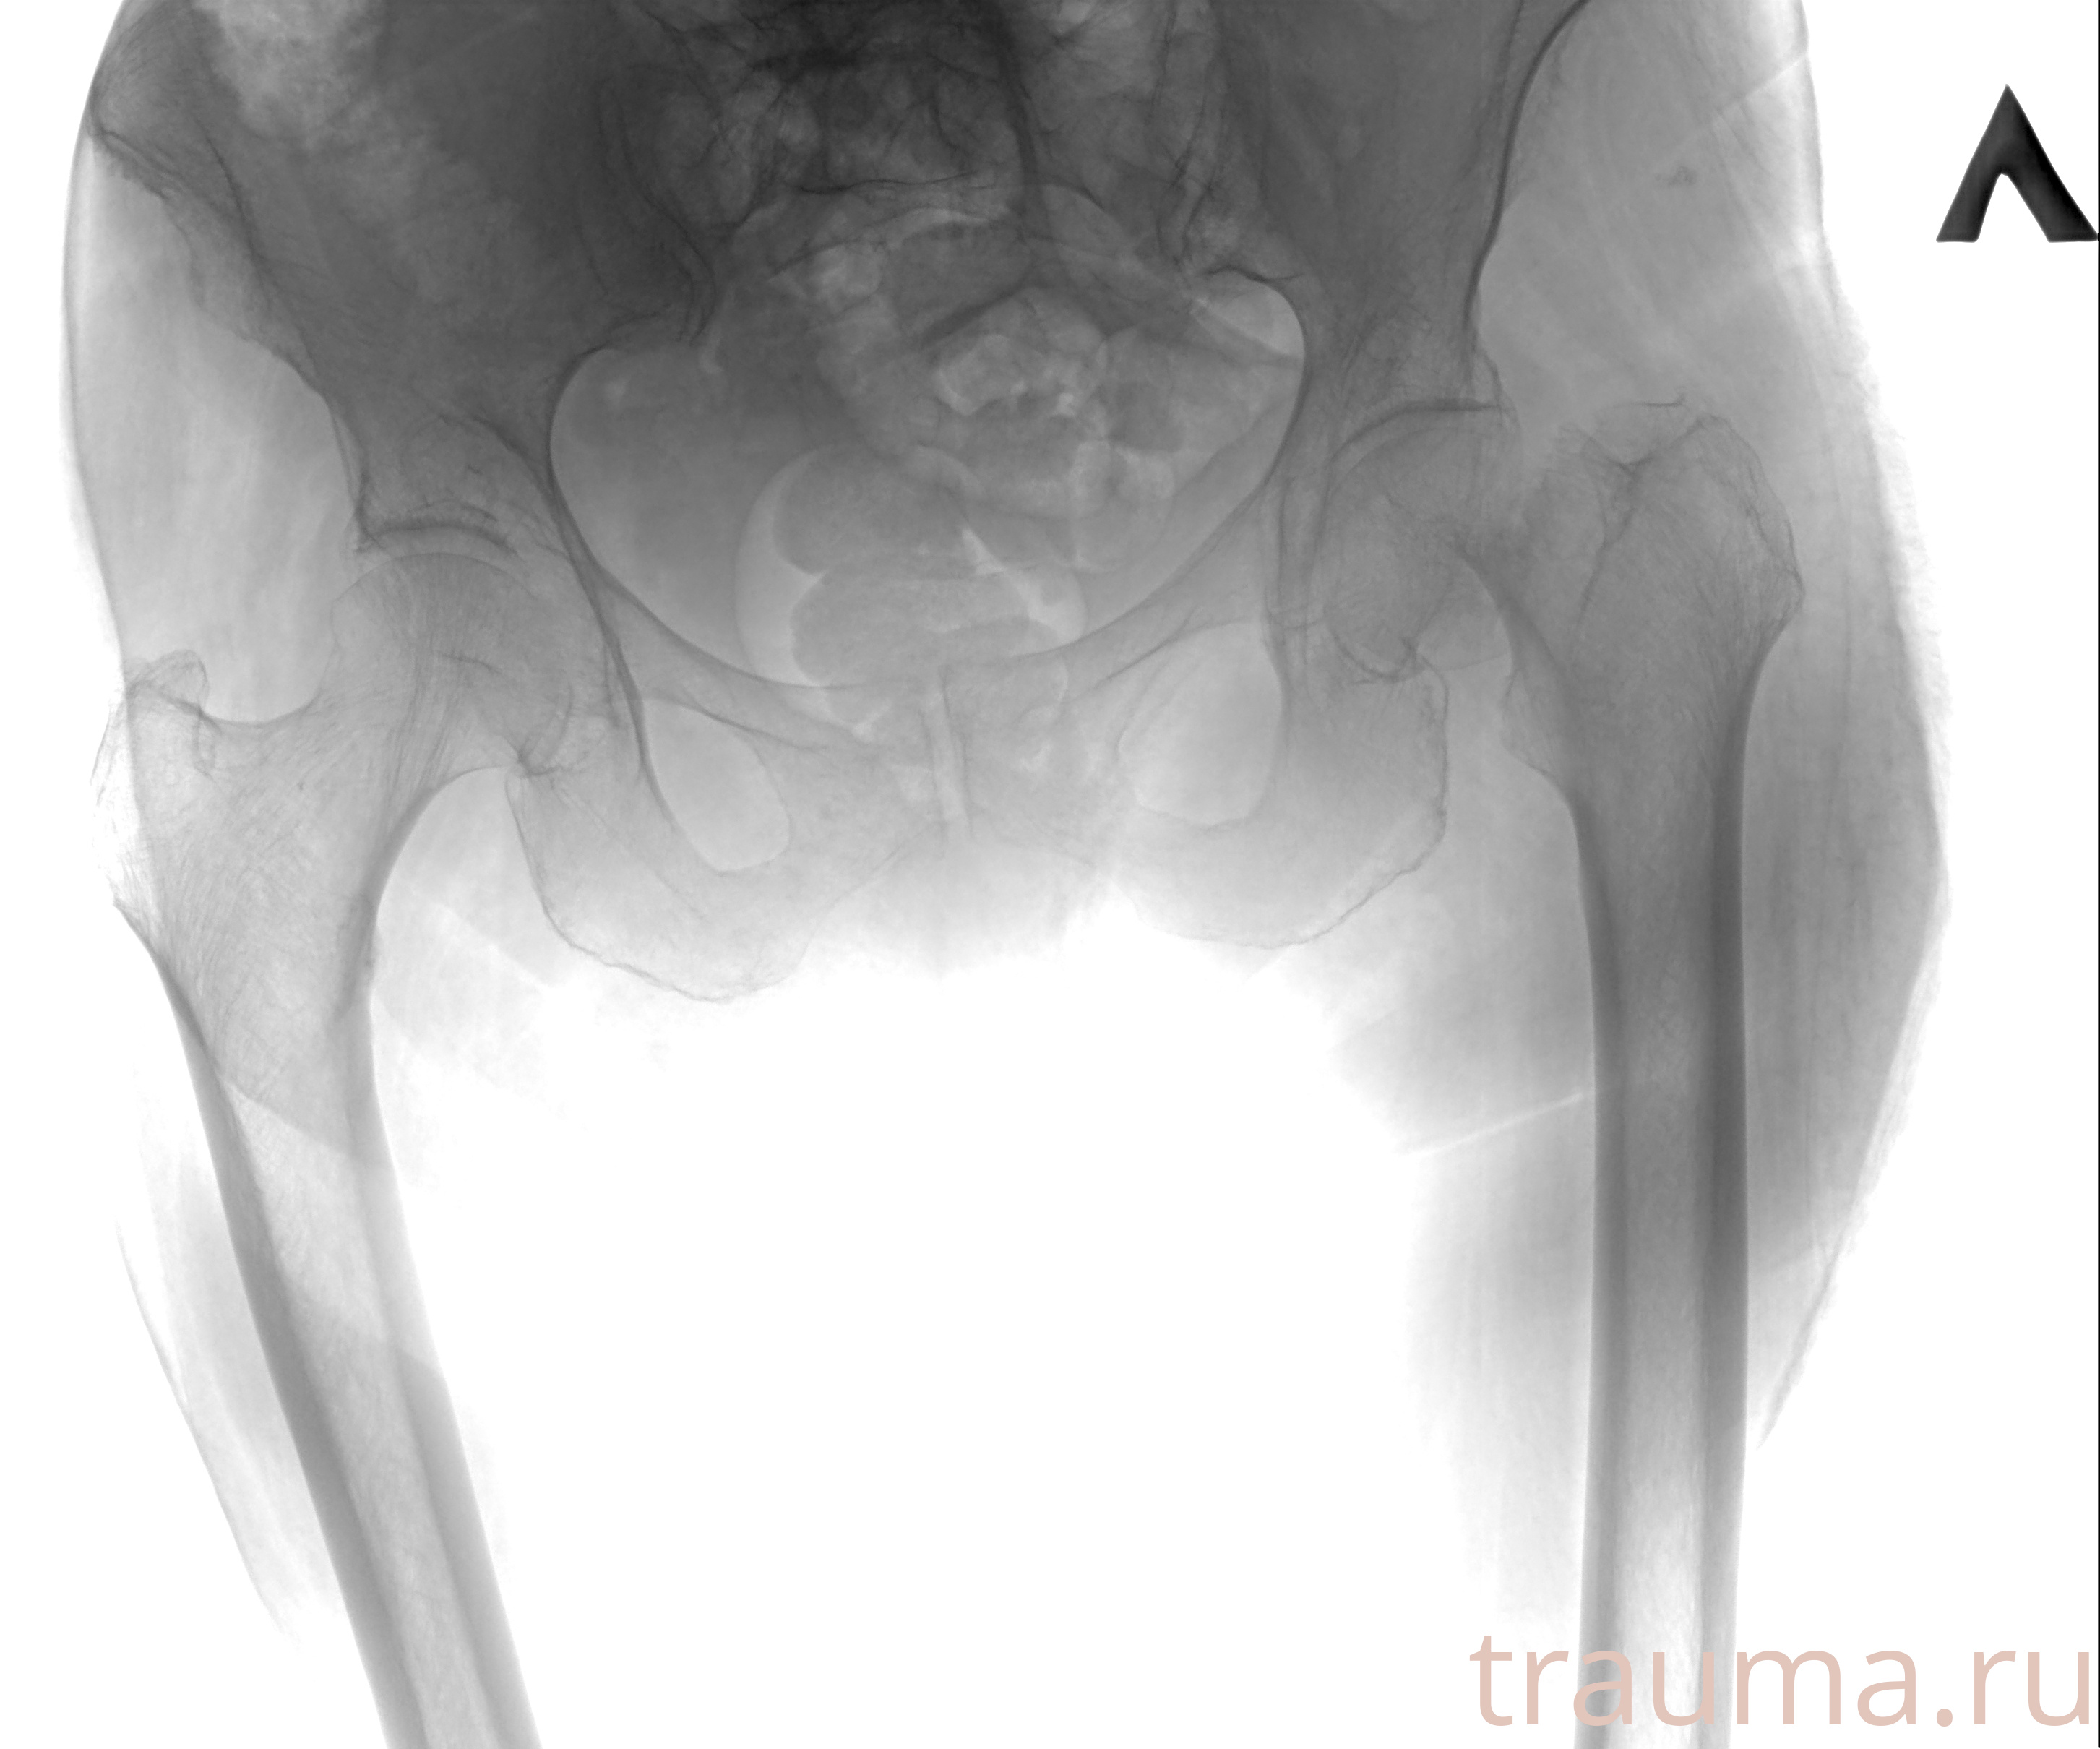

Рентгенограммы

Рентген на дому: по вашему адресу приезжает врач-рентгенолог, травматолог-ортопед с мобильным рентгеновским аппаратом, проводит диагностику травмы или заболевания, делает необходимые рентгенограммы, дает рекомендации по дальнейшему лечению. Получить качественные снимки в домашних условиях возможно благодаря уникальной методике, разработанной МосРентген Центром для института  Склифосовского